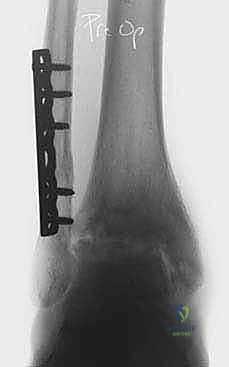

- الأشعة السينية (X-rays) مع الوقوف: لتقييم المسافة المتبقية من المفصل وتحديد درجة الخشونة ومحور الساق.

- الأشعة المقطعية (CT Scan): للحصول على صورة ثلاثية الأبعاد للعظام، واكتشاف أي تكيسات عظمية (Bone cysts) أو نتوءات عظمية (Osteophytes).

الخطوة الثانية: تركيب الإطار الخارجي (Ilizarov Frame)

هذه هي المرحلة الهندسية الدقيقة. يتم تركيب حلقتين معدنيتين حول عظمة الساق (Tibia) وحلقة ثالثة حول القدم (تثبت في عظمة العقب Talus وعظام مشط القدم).

الخطوة الثالثة: إدخال الأسلاك والمسامير (Wire and Pin Placement)

يتم تمرير أسلاك معدنية رفيعة جداً (Kirschner wires) ومسامير نصفية (Half-pins) عبر العظام لتثبيت الحلقات. يعتمد الأستاذ الدكتور محمد هطيف على معرفته التشريحية العميقة واستخدام جهاز الأشعة المرئي (C-arm) لضمان مرور هذه الأسلاك في "الممرات الآمنة" (Safe corridors) بعيداً عن الشرايين والأعصاب الحيوية.